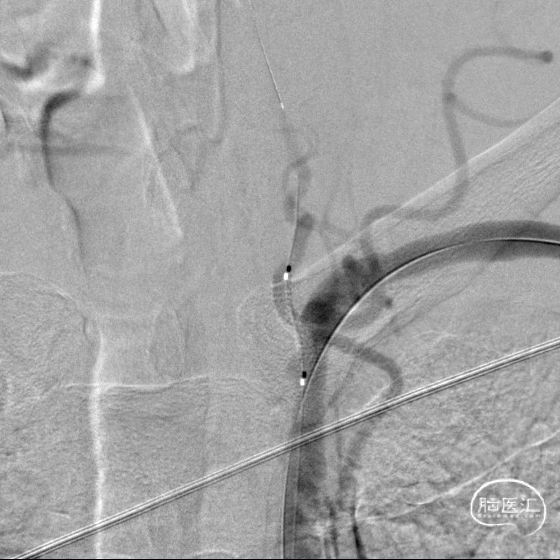

DSA:LSub。

DSA:L-CCA。

0.018*300cm 外周导丝至左肱动脉,0.014*200cm 通桥北斗SS™神经血管导丝超选至左椎V2段远端。

沿0.018*300cm 外周导丝送入6*40 外周球囊送至左侧锁骨下动脉狭窄处,压力泵逐渐加压到6atm。

撤出球囊后见残余狭窄40%。

再次沿0.018*300cm 外周导丝送入6*40 外周球囊达LSub狭窄部位,压力泵逐渐加压到8atm,见残余狭窄20%。